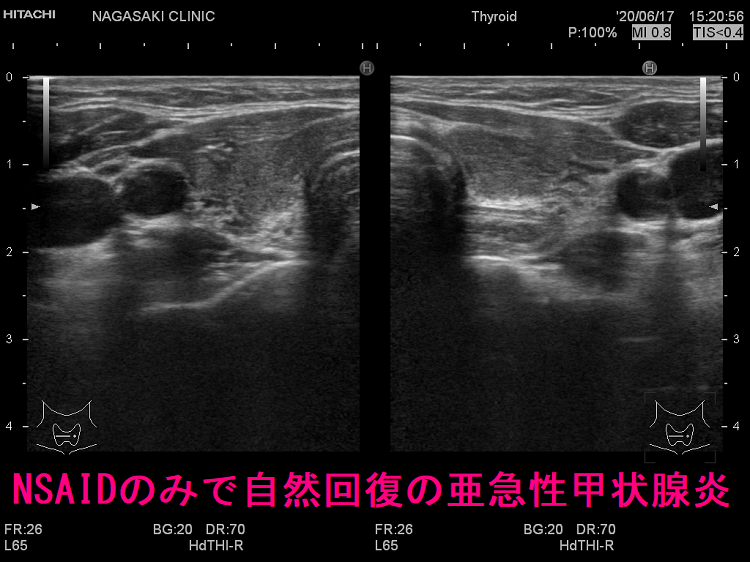

ロキソニンなどの抗炎症薬(NSAIDs)は、痛みを和らげる・熱を下げる対症療法で、亜急性甲状腺炎自体の炎症を抑えません。抗炎症薬を使用するのは、

- 副腎皮質ホルモン剤(ステロイド剤)の副作用などが危惧されたり、高齢(次項)などの理由で、同剤を3-4か月投薬できない

- 非常に軽度の亜急性甲状腺炎で、副腎皮質ホルモン剤(ステロイド剤)を投与しなくても自然治癒する可能性が高い